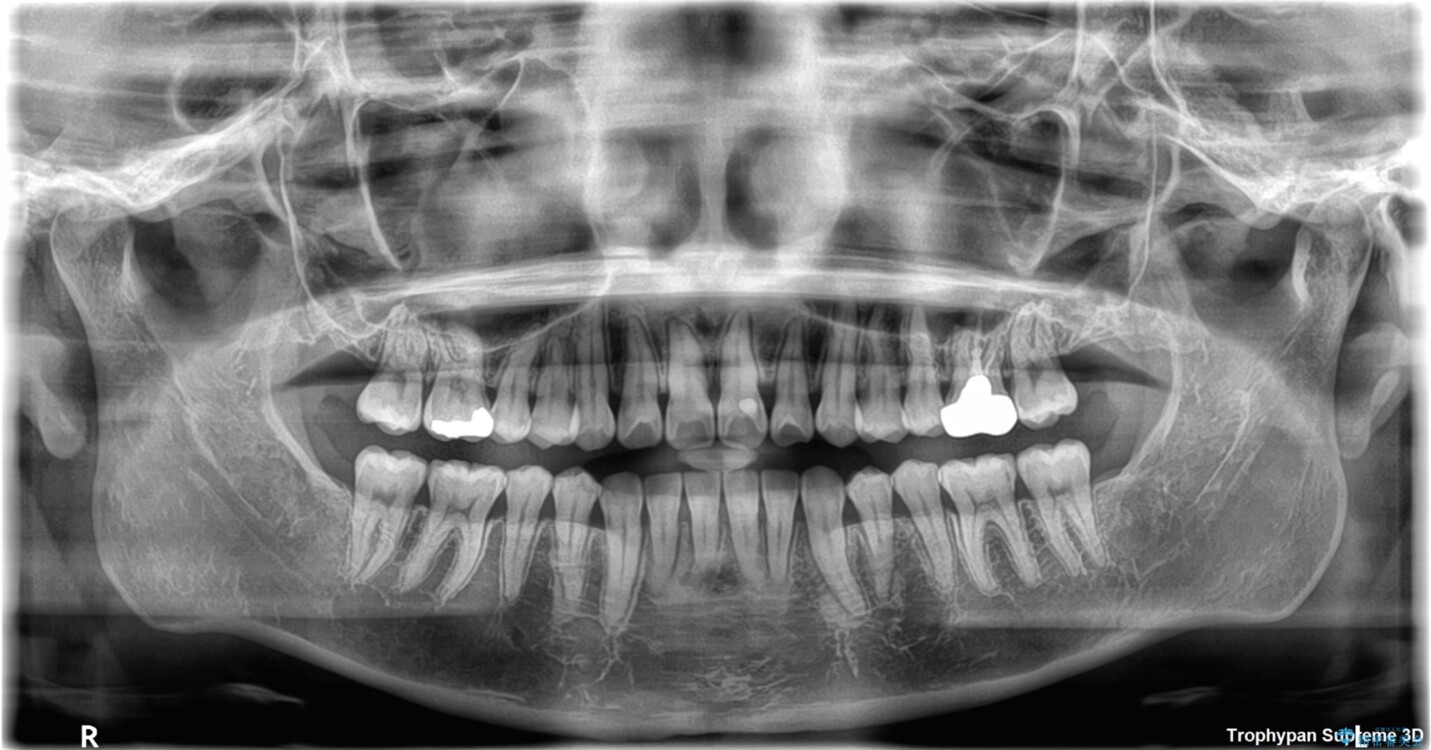

◆ 診断と治療計画

診察の結果、上下の前歯部に**叢生(そうせい/歯のガタガタ・重なり)**が認められました。

特に上の前歯にはねじれや重なりがあり、審美的にも清掃性にも影響している状態でした。

治療方法としては、装置の目立ちにくさと費用面のバランスを考慮して、プラスチック製のクリアブラケットとメタルワイヤーを組み合わせた矯正装置を使用することにしました。

また、上顎前歯の重なっていた部分にはむし歯が見つかり、治療中に適切な処置を行っています。